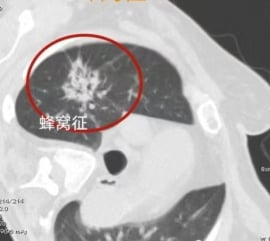

蜂窝征:从磨玻璃到实性的演变

蜂窝征是指病灶内部密布着众多微小空泡,整体呈现出蜂窝状图案,通常为实性或倾向于实性密度。在早期,这类病灶常被误判为炎症。然而,随着研究深入,我们认识到这类病灶绝大多数具有恶性潜能,可能经历了从磨玻璃样改变向更致密实性病灶的演变。当部分区域尚未完全密实,呈现出类似蜂窝的外观时,这往往强烈提示黏液样癌的可能性较高。因此,对于具有这种独特影像学特征的病灶,应保持高度警惕,以便及时采取恰当的诊断与治疗措施,尤其是在肺癌的鉴别诊断中。